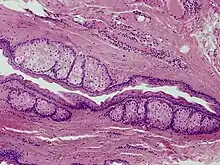

The cysts are mostly small (2–20 mm) but they may be several centimetres in diameter. They tend to be soft to firm semi-translucent bumps, and contain an oily, yellow liquid. Sometimes a small central punctum can be identified and they may contain one or more hairs (eruptive vellus hair cysts). They may become inflamed and heal with scarring, like acne nodules (see nodulocystic acne and hidradenitis suppurativa).

Steatocystomas are thought to come from an abnormal lining of the passageway to the oil glands (sebaceous duct).